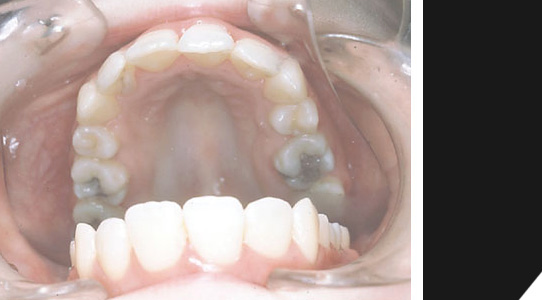

Schneidezähne oben stehen zu eng, untere Front besteht nur aus drei Zähnen.

Im unteren Bereich sind nur drei Frontzähne vorhanden...